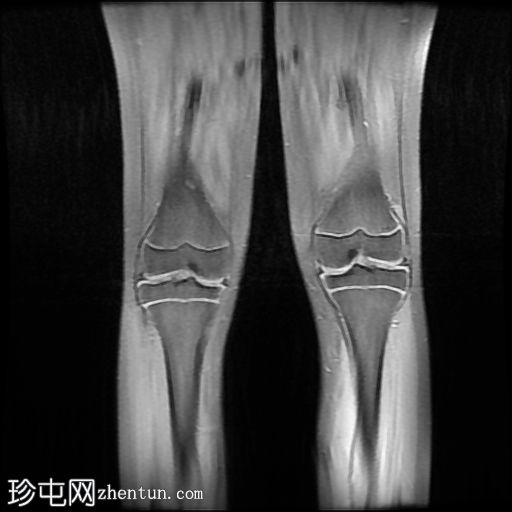

MRI

冠状面

T2

股骨远端和腓骨近端干骨干部边界清晰的皮质性病变在T1加权图像上主要表现为低信号强度,在T2加权图像上表现为中等/混合信号强度,周边强化较小。胫骨结节骨髓水肿(STIR 和 T1FS/T1+C FS 可见),且无明显软组织肿胀/水肿或远端髌腱增厚/水肿,提示胫骨结节骨骺炎。